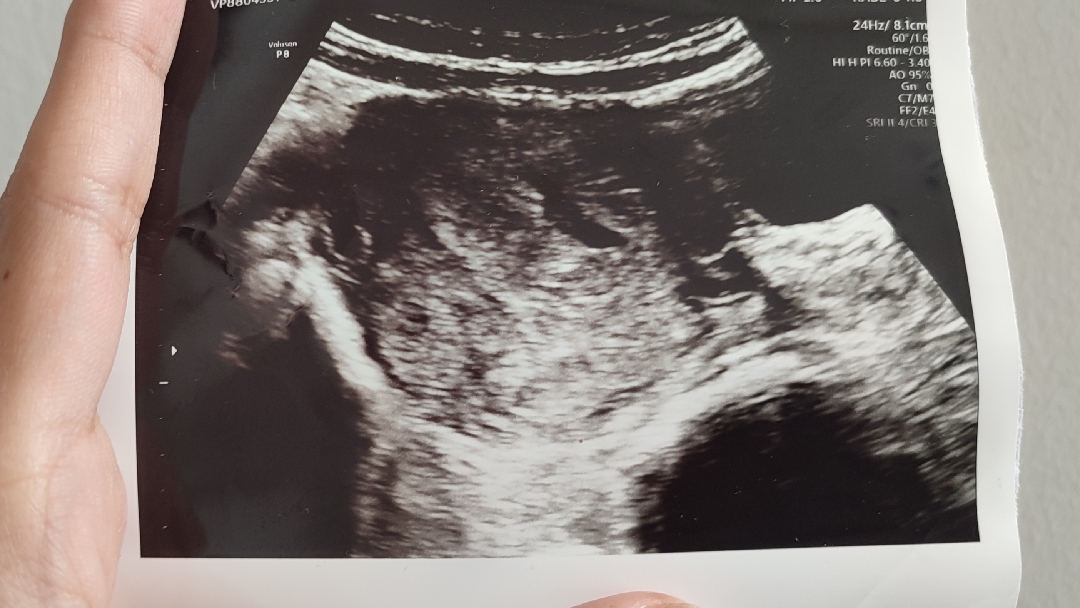

Hasil USG belum jelas di minggu ke 4

Mom, mau tanya dong, tgl 12 kemaren positif hamil hasil testpeck. Ke klinik katanya positif, trs hri ini aku USG tapi masih belum keliatan jelas. Kira kira wajar gaa ya?

Kalau tadi kata dokternya si perkiraan kantungnya yg agak lonjong ditengah ituu kaya terong. Tapi masih praduga karna belum terlihat jelas infonya

Oh itu ya kak yg sedikit kayak bolong giti

Iyaaa bun betul